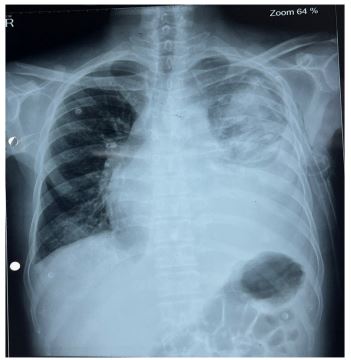

Figure 1: Chest X-ray PA view showing cardiomegaly with enlarged cardiothoracic ratio. The left upper lobe shows fibrotic changes post-pulmonary tuberculosis.